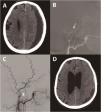

ResultsFifteen patients underwent MMA embolization, with a predominance of males (80%) and a mean age of 72.4 years. The most common presenting symptom was headache (53.3%). The average hospital stay was 3.9 days. Various embolization techniques were employed, with DMSO-EVOH being the most frequent. All procedures were successfully conducted without complications. Although not statistically significant, trends suggested better outcomes in patients with homogeneous cSDH on the CT scan, displaying the cotton wool sign on angiography and treated with EVOH-DMSO.

Resultados15 pacientes se sometieron a embolización de la AMM, con un predominio de hombres (80%) y una edad media de 72,4 años. El síntoma de presentación más común fue la cefalea (53,3%). La estancia hospitalaria media fue de 3,9 días. Se emplearon varias técnicas de embolización, siendo el DMSO-EVOH la más frecuente. Todos los procedimientos se llevaron a cabo con éxito y sin complicaciones. Aunque no fue estadísticamente significativo, se observaron mejores resultados en pacientes con HSDc de aspecto homogéneo, en aquellos que presentaban el signo del cotton-wool y en los tratados con EVOH-DMSO.